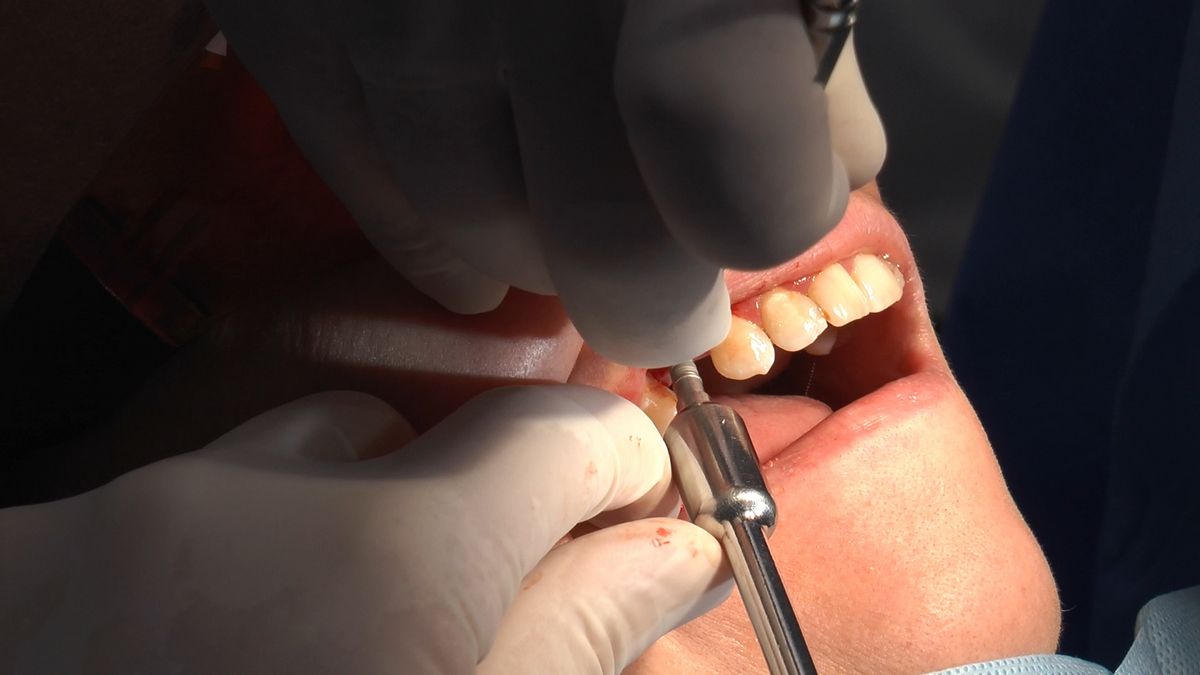

W ostatni weekend czerwca 2018 roku kursanci II Sezonu Preludium Implantologii odbyli piątą, finałową sesję, która w całości podporządkowana była praktyce. W ciągu dwóch dni zabiegowych Lekarze uczestniczący w szkoleniu przeprowadzili szereg zabiegów pod kierunkiem dr n.med. Violetty Szycik. Wszczepili 17 implantów oraz przeprowadzili ekstrakcje i zabiegi regeneracyjne kości. Zabiegi były wykonywane także w sedacji dożylnej z udziałem specjalisty anestezjologii i intensywnej terapii dr Jolanty Grzybowskiej. Preludium implantologii to nowy program edukacyjny dla adeptów implantologii stomatologicznej, którego celem jest wprowadzenie do implantologii poprzez pozyskanie wiedzy w szerokim zakresie i uwzględnieniem szczegółów mających decydujące znaczenie dla powodzenia leczenia implantologicznego. Ale tak jak wszystkie szkolenia w Instytucie Vivadental, w tym wiodące Practiculum Implantologii, zorientowane jest na praktyce i samodzielnym wykonywaniu zabiegów pod kierunkiem Mentora. To najlepsza edukacja w medycynie zabiegowej, a zarazem najlepszy start do implantologii.